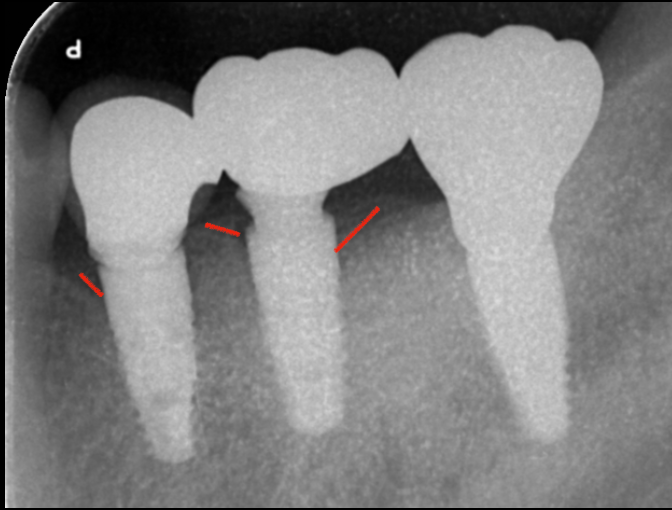

骨縁から離して周囲炎リスクを低減する結合部設計

この歯肉がアバットメントに付着することで、細菌の感染を防ぐ防御壁となってくれます。一番右のインプラントが当院で埋入したインプラントです。

他の二つのインプラントに比べて骨吸収がなく、インプラント結合部が十分に骨縁から離れているのが見てとれます。

これによりインプラント周囲炎が起こりづらい構造となっております。